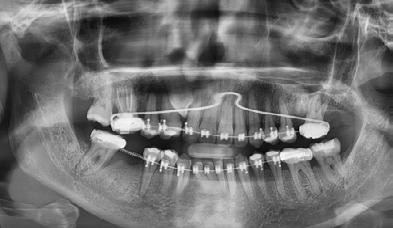

Se presenta una paciente de 52 años de edad, con tratamiento previo inconcluso. Es diagnosticada en el CESO con clase II esquelética, de crecimiento hiperdivergente, biotipo dolicofacial, con clase III canina y molar izquierda, clase III molar derecha, canino 13 retenido, mordida abierta anterior, ausencia de molares 26 y 46.

Tratamiento: extracción del canino 13, alineación, nivelación, cierre y manejo de espacios, detallado y retención. Aparatología: brackets prescripción Roth 0.022 × 0.028", tubos bondeables en 6's y 7's, micrototnillo extralveolar de 2 × 14 mm. Objetivos: corrección del perfil labial, obtención clase I molar izquierda, clase I canina bilateral, corrección del apiñamiento mandibular, del overjet y overbite, de líneas medias dentales, caracterización del primer premolar 14 por canino 13, mantener espacio entre 45 y 46. Tiempo de tratamiento, 2 años 11 meses.

Se presenta una paciente de 52 años la cual menciona que ya había recibido un tratamiento previo de ortodoncia que quedó inconcluso, actualmente todavía tiene los braquetes de ese tratamiento. Pero ahora ella quiere iniciar un nuevo tratamiento en el CESO con el fin de mejorar su mordida. Es diagnostica con clase II esquelética, de crecimiento hiperdivergente, biotipo dolicofacial, clase III canina y molar izquierda,

clase III molar derecha, canino 13 retenido, mordida abierta, ausencia de los molares 26 y 46.

Estudios radiográficos de inicio

En la radiografía panorámica (Figura 5) se observan en 20 dientes los brakets viejos, en los molares 16, 27 las bandas, el canino 13 retenido en el paladar, el botón de Nance, la

ausencia de molares 26, 46. Elmolar 16 tiene un tratamiento endodóntico

14 para la caracterización del canino 13, (Figura 6) IPR y elásticos clase III para corrección de overjet, elásticos asimétricos y uso de microtornillos de 2 × 14 mm en cresta infracigomática izquierda para corrección de línea media, arcos de acero 0.017 × 0.025 y 0.019 × 0.025 con dobleces de primer, segundo y tercer orden para detallado, retención a cargo de retenedor fijo inferior de 3 a 3, retenedor circunferencial superior y termoformado inferior.

El tiempo del tratamiento fue de 2 años 11 meses, en la Figura 7 en los

estudios extraorales finales se ve la mejoría en la sonrisa y de los tejidos blandos en cuanto al perfil facial.

Estudios intraorales finales: se observa en la Figura 8 y 9 la mordida del paciente en oclusión las lineas medias coincidentes, formas de las arcadas oval, la obturacion del molar 26, la clase I canina y molar izquierda, clase I canina derecha, caracterización de premolar 14 por canino 13, clase I molar derecha y espacio en el cuandrante 4 el cual se utilizará para rehabilitación protésica.

Estudios radiográficos finales: se observa en la Figura 10 en la

radiografía lateral de cráneo la mejoría en la inclinación del incisivo inferior.

En las radiografías panorámicas (Figura 11), en la comparación inicio el botón de Nance, en la final se ve sin el canino retenido, el paralelismo radicular, con la ligera perdida ósea con la que llegó la paciente en la zona antero inferior y cuadrante 4, al final continúa sin cambios.

Figura 11. Comparativa Rx Panorámica inicio final.